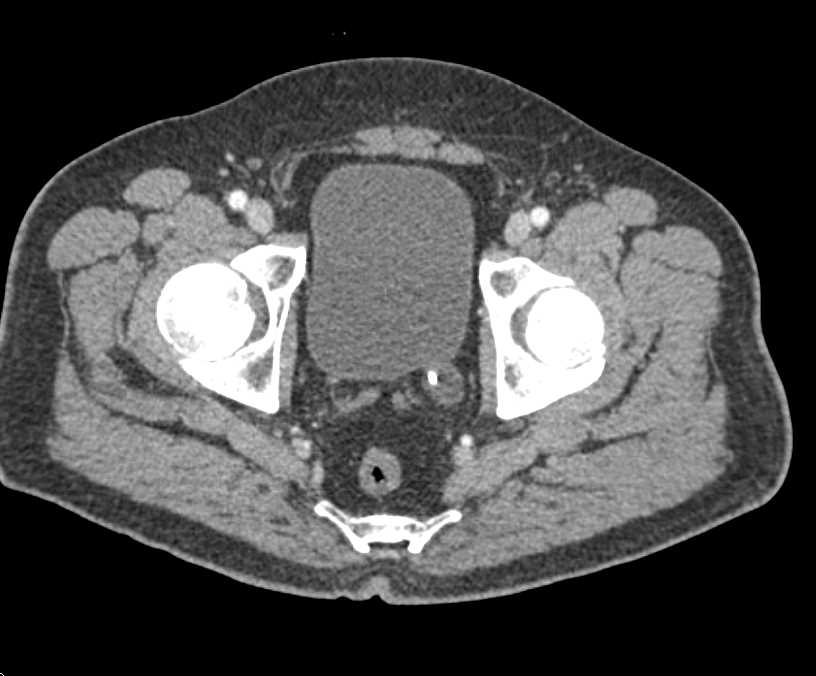

1cm Vascular Metastases Near Right Renal Bed in Patient with Renal Cell Carcinoma and Nephrectomy